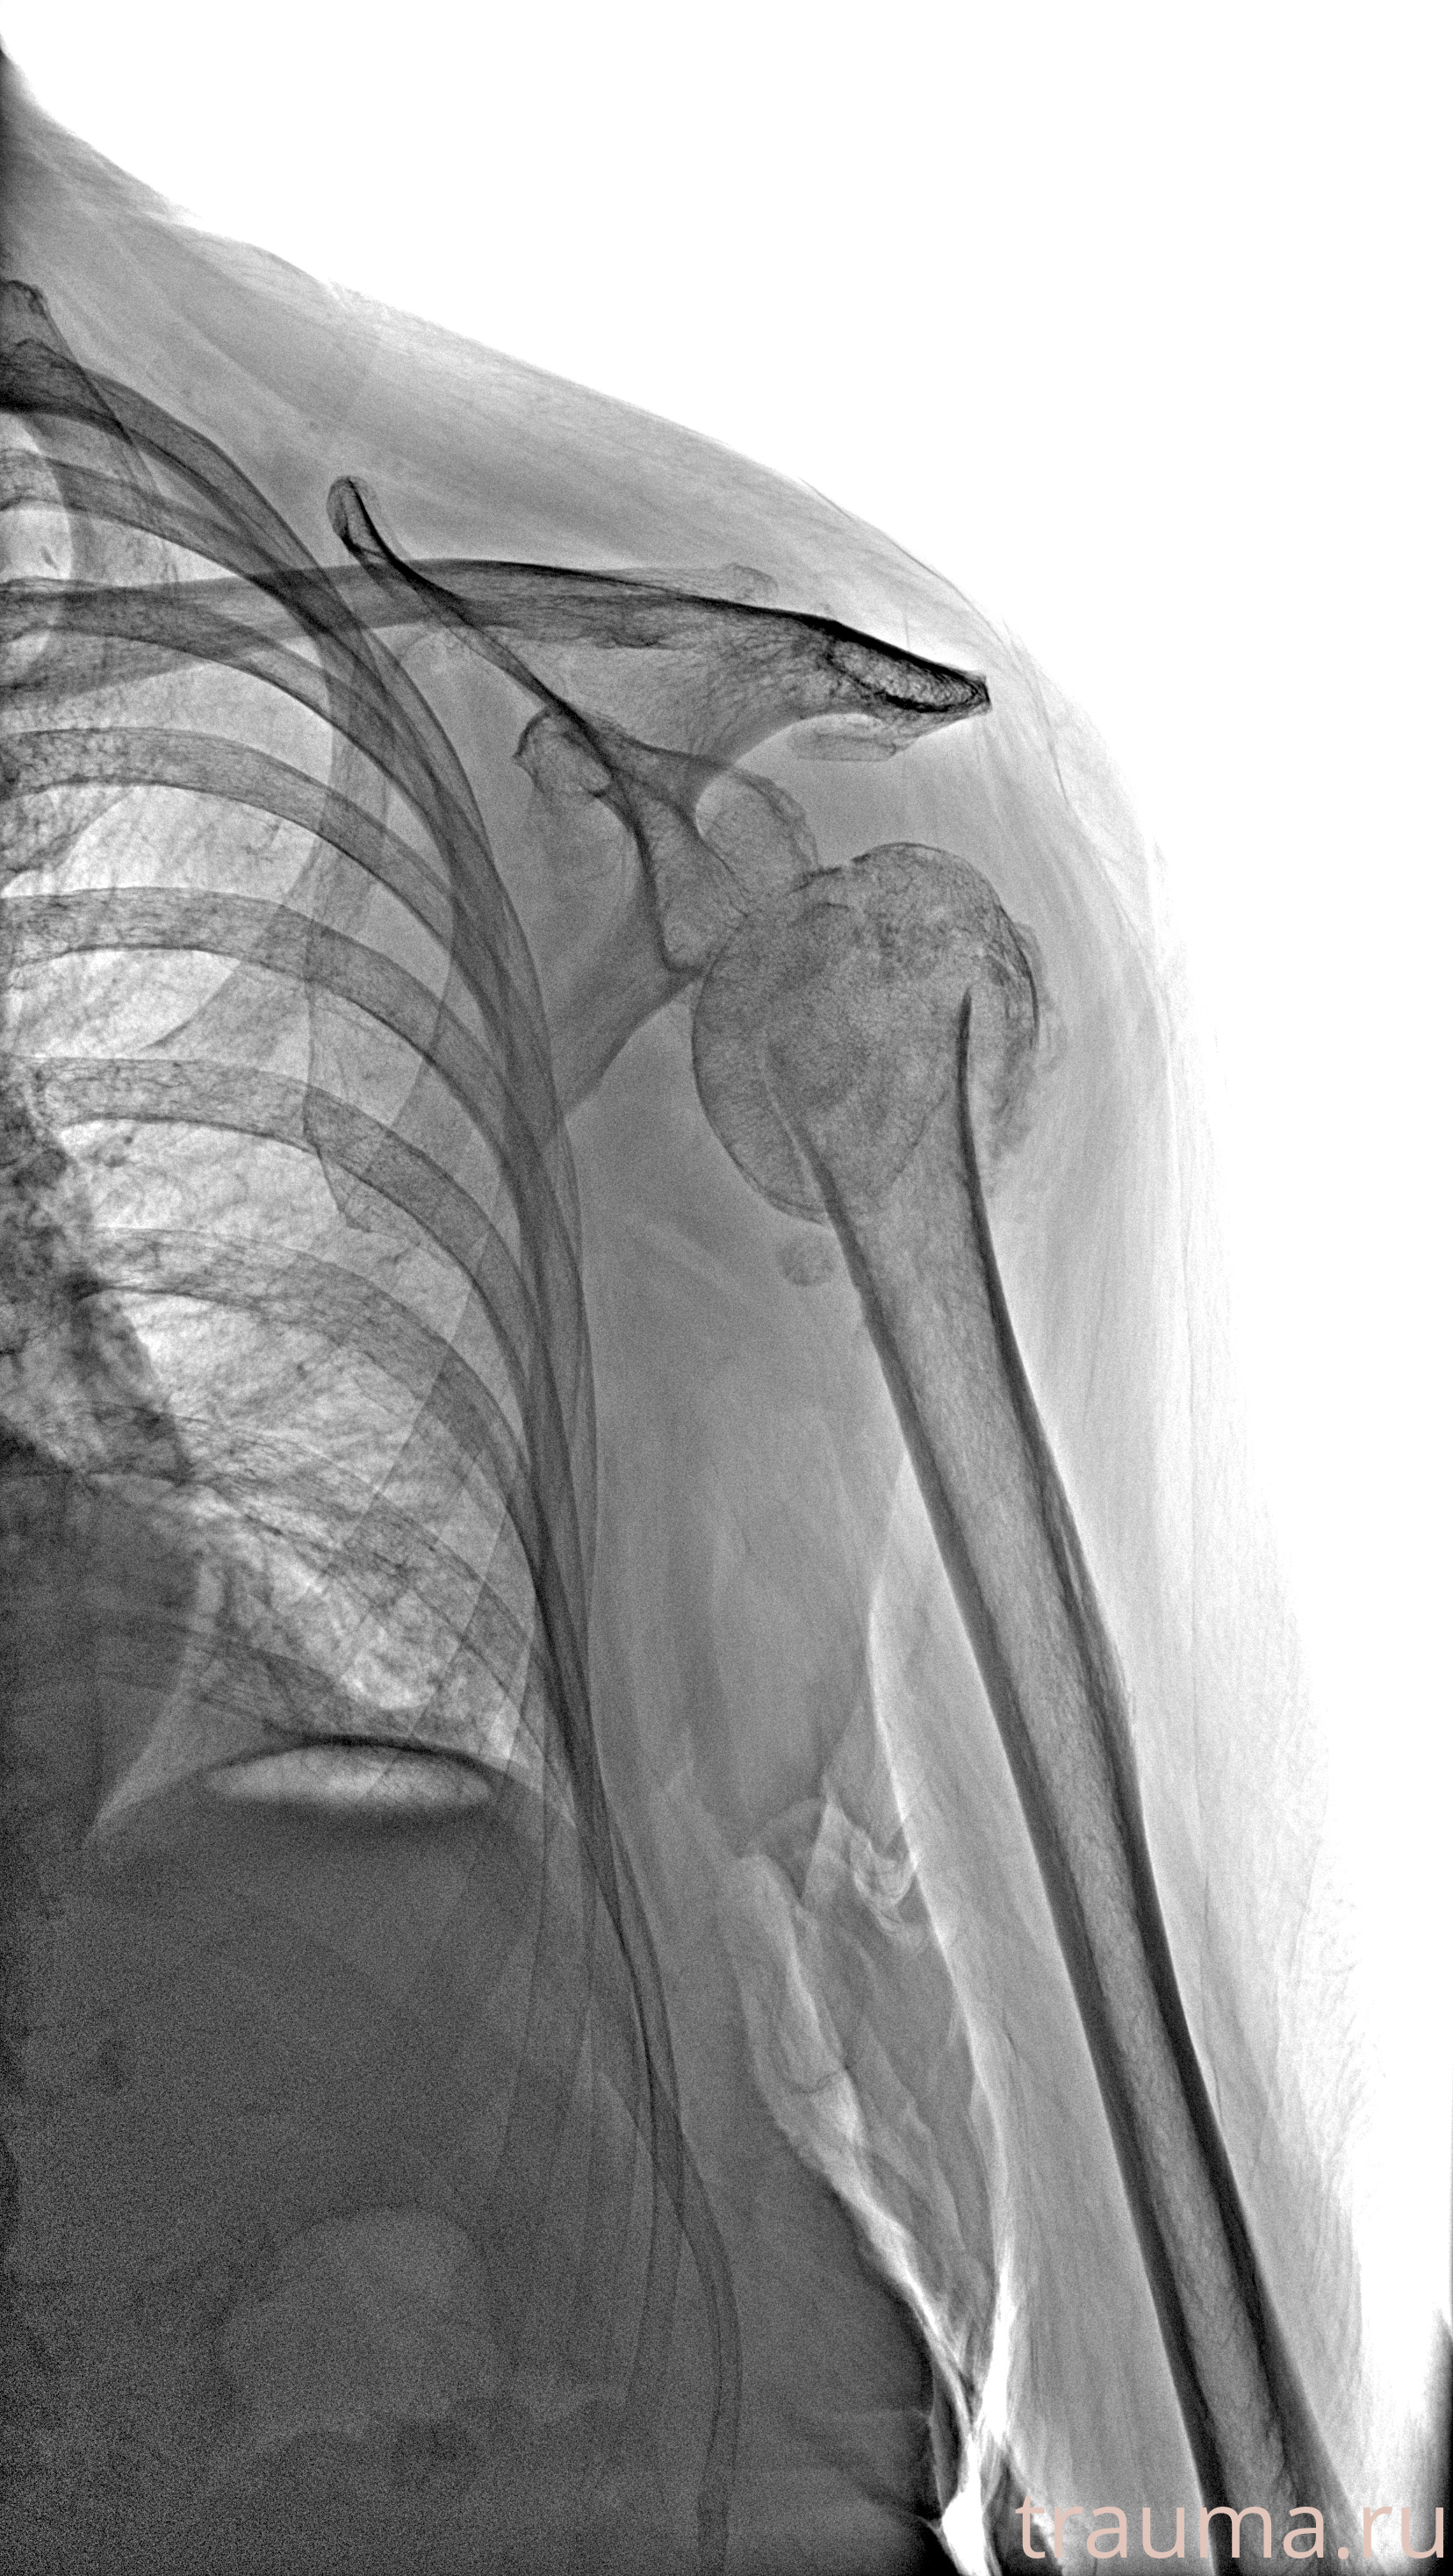

Рентгенограммы

Рентген на дому: по вашему адресу приезжает врач-рентгенолог, травматолог-ортопед с мобильным рентгеновским аппаратом, проводит диагностику травмы или заболевания, делает необходимые рентгенограммы, дает рекомендации по дальнейшему лечению. Получить качественные снимки в домашних условиях возможно благодаря уникальной методике, разработанной МосРентген Центром для института  Склифосовского